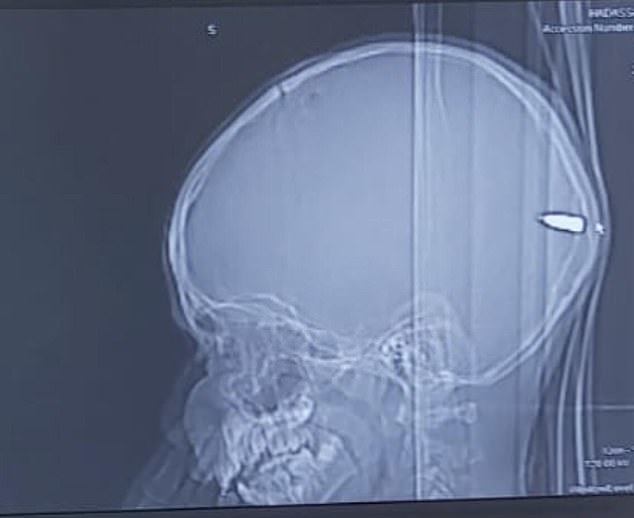

巴勒斯坦一名9岁男孩在和朋友玩耍时突然被什么东西砸了一下 , 随后总是昏昏欲睡 , 提不起精神 。 父母带他去了当地一家医院接受检查 , 不料医生竟在男孩大脑中发现了一颗子弹 , 立即通过手术方式取了出来 。 负责手术的医生盖伊·埃洛表示:“男孩能活着堪称是奇迹 , 幸运的是手术非常成功 , 男孩脱离了生命危险” 。 据分析 , 男孩中枪的原因很可能因为当地人在庆祝活动中鸣枪 , 男孩被流弹击中 。

盖伊·埃洛是是负责这场手术的神经外科医生 , 他介绍道:“男孩来自东耶路撒冷 , 父母把他送到哈达萨医疗中心时男孩意识清醒 。 但我们发现他头上有一个微小的伤口 。 我们检查发现子弹从男孩头骨一侧进入 , 穿过他的大脑 , 在后脑勺附近停止 , 男孩的父母完全不知道儿子中枪了 。 男孩的母亲说男孩当时正在和朋友玩耍 , 突然说有什么东西砸到了他的头 , 但因为只有一个小伤口 , 我们都没有在意” 。

男孩能活下来堪称奇迹 , 因为如果子弹从另一个角度射入就会对大脑造成严重伤害 , 并造成神经损伤 , 如今男孩已经脱离了危险 。